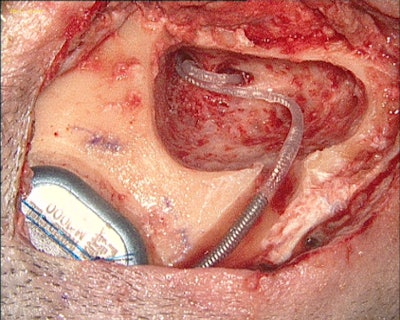

Auditory Brainstem Implants

Auditory brainstem implants directly stimulate the cochlear nucleus. They are surgically implanted at the lateral recess of the fourth ventricle. Their main indications are patients with no cochlear nerve, cochlear aplasia, or cochlear ossification. The surgery implies a neurosurgical access, through a retrosigmoid or translabyrinthine approach. This device offers improvement if implanted in children. In most cases, children perceived sound and some conversational cues.